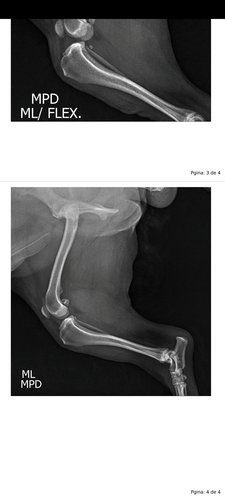

Infelizmente meu cachorro Pop rompeu o ligamento do joelho e precisa de uma cirurgia o mais rápido possível.